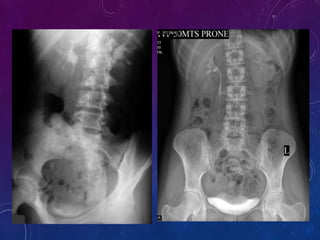

 Plain X-Ray KUB/Scout film -14x17

Plain X-ray KUB /Scout film provides valuable information and sometimes

indicates provable diagnosis.

Useful in assessing :

1) Calculus

2) Intestinal abnormalities

3) Intestinal gas pattern

4) Calcification

5) Abdominal mass

6) Foreign body

15 minutes film :

1) Visualization of ureter is better in prone position as the fill better.

2) This position reverses curve of the inferior course of the ureters making it

anti-dependent is to gravity.

3) Another method to see ureter is modified trendelenberg technique with 15-20

degrees head low tilt with the patient supine.

30 minute film:

1) It gives complete over view of the urinary tract ; Kidneys,Ureters,Bladder.

Bladder distension can be evaluated